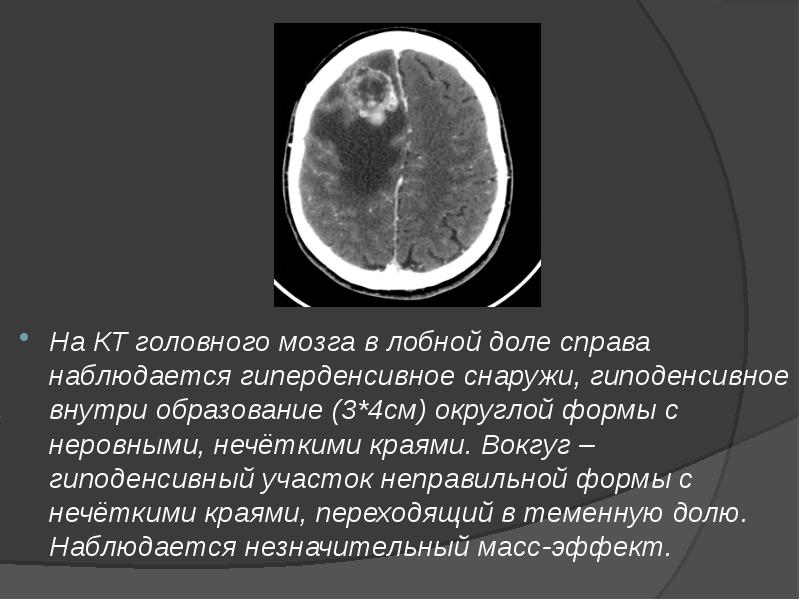

- 14. На КТ головного мозга в лобной доле справа наблюдается гиперденсивное снаружи,